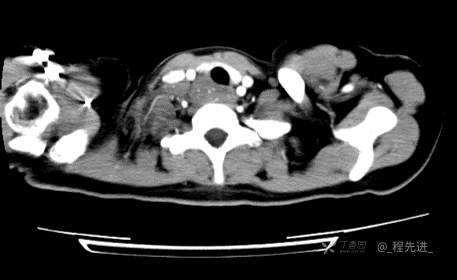

患者性别:女

患者年龄:26岁

简要病史:反复胸闷、气喘、咳嗽半年